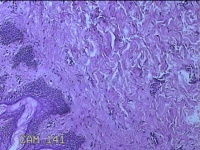

左侧腋下结节

性别

女

年龄

22岁

临床诊断

皮下结节;皮脂腺囊肿

一般病史

发现左侧腋下结节伴隐痛不适1周余。

标本名称

大体所见

灰白暗红色带皮肤样结节2.5x1.5x0.7cm一个,表面糜烂,切开结节呈实性,切面灰白淡黄色,质软。

图2